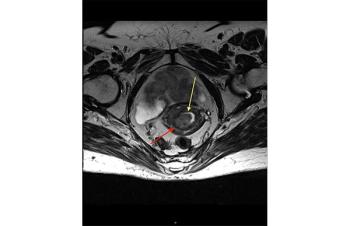

Diagnosis of endometrial carcinoma made easier by analysis of mutations in cervix or endometrial tissue.

The AVANOVA2 trial enrolled a total of 97 patients with high-grade serous or endometrioid platinum-sensitive recurrent ovarian cancer.

The first-of-its-kind collaboration led to the approval of a combination therapy for patients with endometrial cancer.